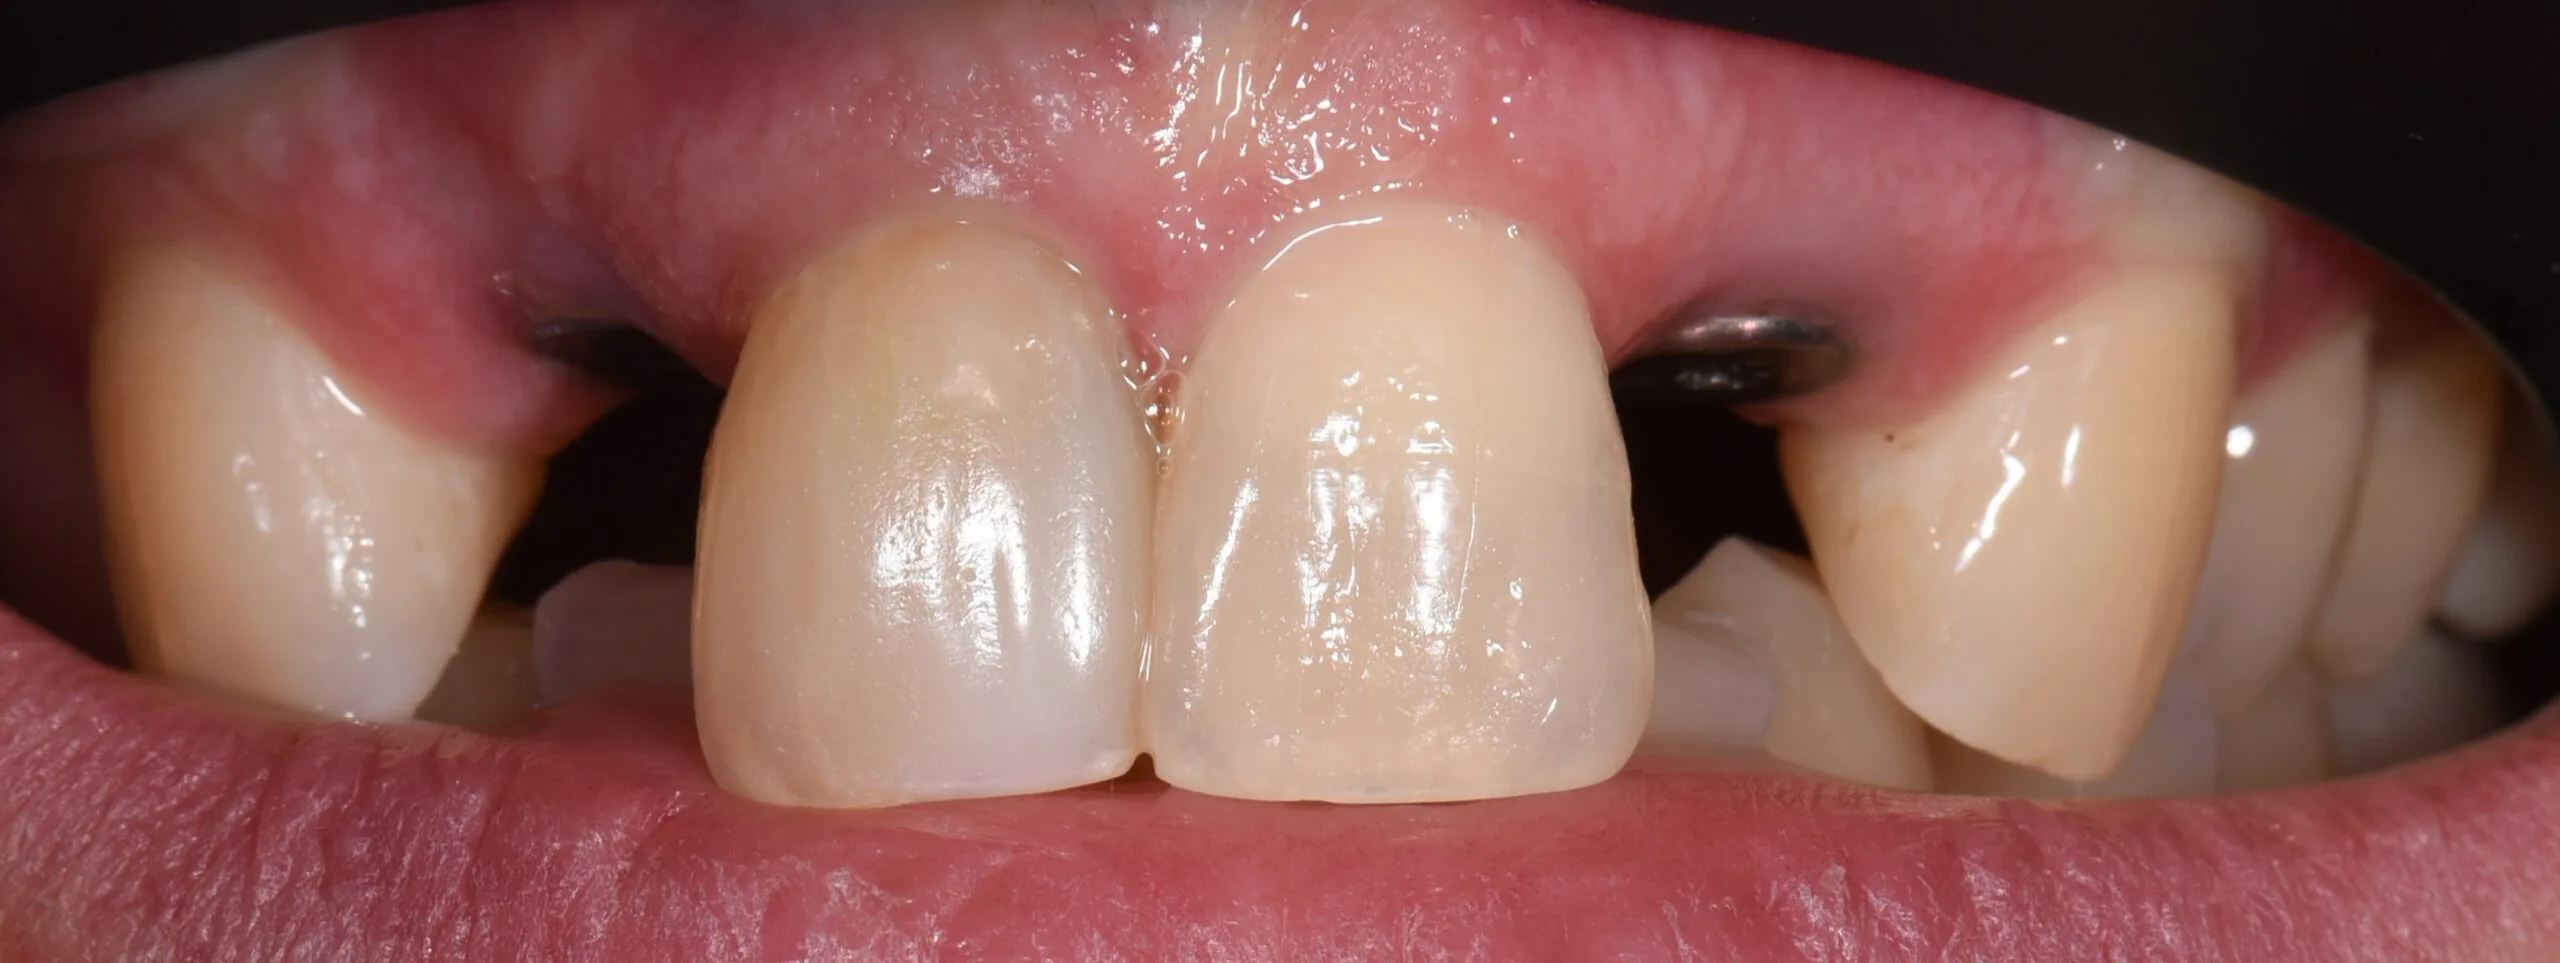

Pacientė kreipėsi dėl skilusių 12 ir 22 dantų šaknų, todėl jautė skausmą ir reikėjo skilusius dantis pašalinti. Pašalinus, buvo įsriegti implantai, jiems prigijus, suformuotos gijimo galvutės ir pritaikyti laikini vainikėliai ant implantų, kad pacientė priprastų prie naujų dantų formos ir pritaikytos spalvos. Net laikinų restauracijų sunku atskirti nuo natūralių dantų ir galime pilnavertiškai džiaugtis savo dantų būkle.